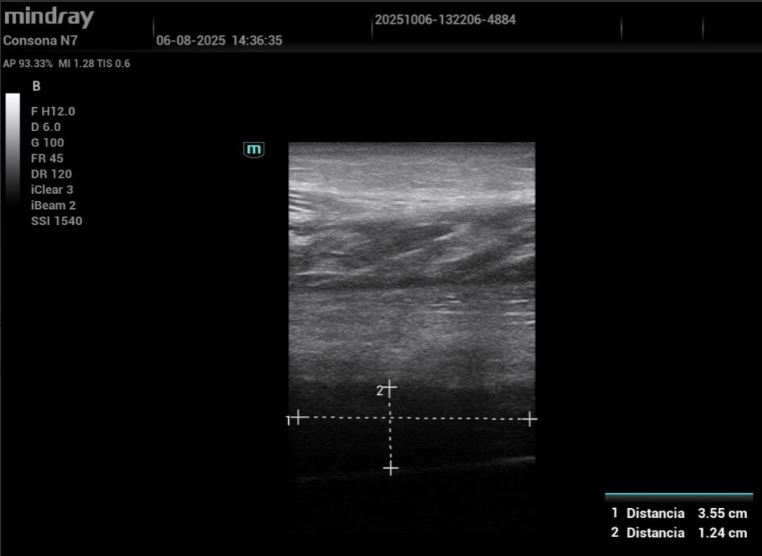

Hombre de 61 años, hipertenso. Consulta por dolor e inflamación en MID tras caída. A la exploración: tumefacción gemelar y calor local. Se realiza ecografía que descarta TVP y muestra rotura fibrilar en músculo sóleo con hematoma intramuscular de 3 cm. Se pauta tratamiento conservador y control evolutivo. Dos semanas después consulta por dolor pleurítico izquierdo sin fiebre ni disnea. A la auscultación: disminución del murmullo vesicular basal. Realizamos ecoscopia que revela derrame pleural moderado, lo que motiva primera derivación a Urgencias para descartar complicación respiratoria.

Hallazgos ecográficos

Eco pulmonar: colección anecoica con pérdida parcial del deslizamiento; compatible con derrame pleural de cuantía moderada.